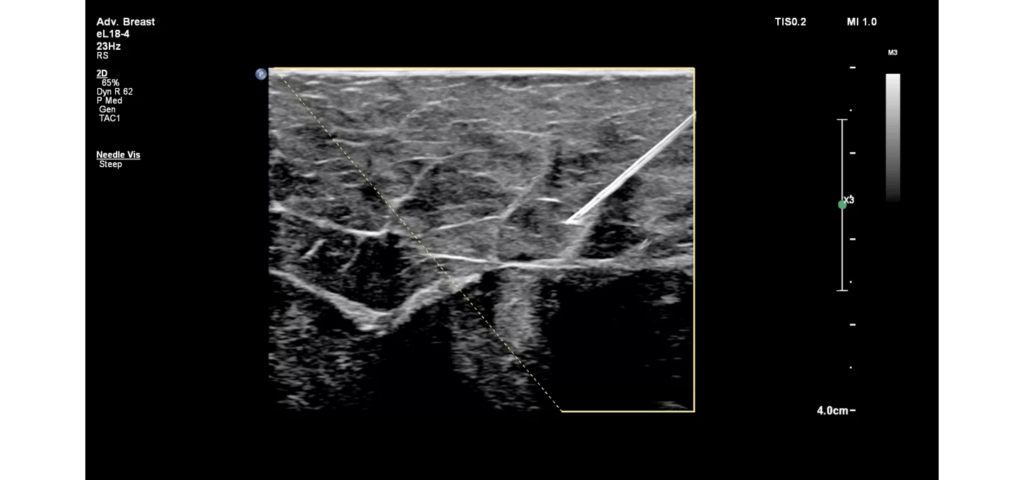

Philips EPIQ Elite ultrasound features an exceptional level of clinical performance, workflow, and advanced intelligence to meet the challenges of today’s most demanding practices. The EPIQ Elite platform brings ultimate solutions to ultrasound, with clinically tailored tools designed to elevate diagnostic confidence to new levels.